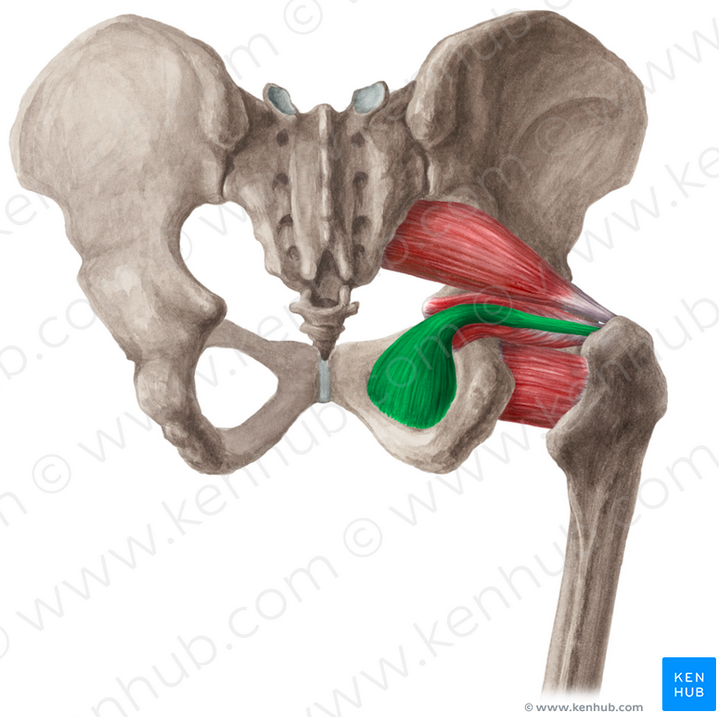

Describe course of obturator internus

origin

Path

Insertion

Origin: ischiopubic ramus & obturator membrane

Path:

THrough lesser sciatic notch

makes a 90 degree turn

Insertion: Medial aspect of GT